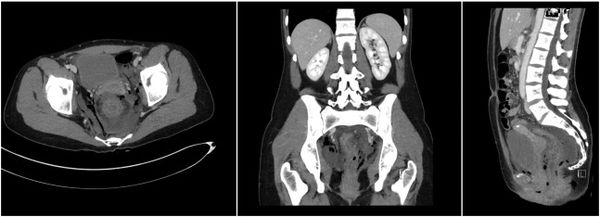

女子被紧急送院后,医生发现她的尾椎骨至肛门口出现长达5公分的伤口,扫描检查结果显示,括约肌和直肠内壁都被撕裂,经过紧急手术缝合后,仍须使用结肠造口袋。

图为患者括约肌和直肠内壁都被撕裂的X光图片。